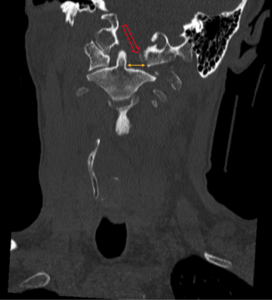

CSpine Fracture CT Coronal Annotated. JETem 2025